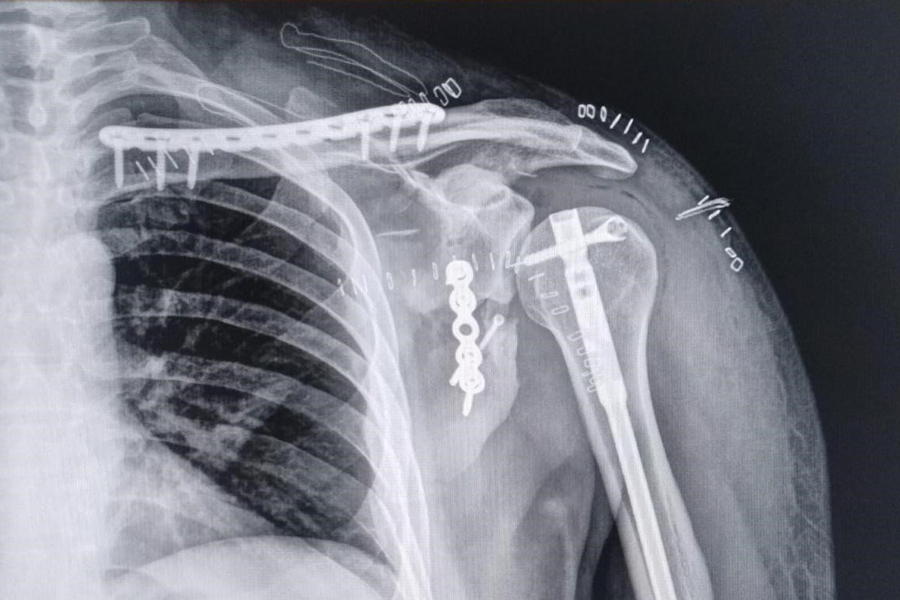

Explicó además que el procedimiento realizado al paciente incluyó “fijación de la fractura de clavícula con una placa deslizada, asegurando estabilidad con mínima agresión a los tejidos. Reparación del húmero con un clavo endomedular que favorece la consolidación ósea. La neurólosis del nervio radial, permitiendo restaurar la movilidad del paciente casi por completo. Y el abordaje posterior de la escápula con técnicas mínimamente invasivas, preservando la biomecánica del hombro y facilitando la rehabilitación”.